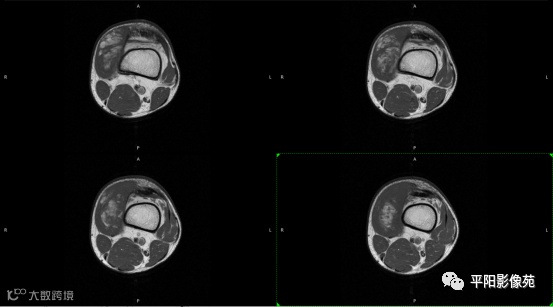

影像表现:

左膝关节股内侧肌内见多房样短T1长T2信号,内可见分隔,增强扫描明显强化,分隔未见明显强化,病灶局部与股骨远端分界不清。